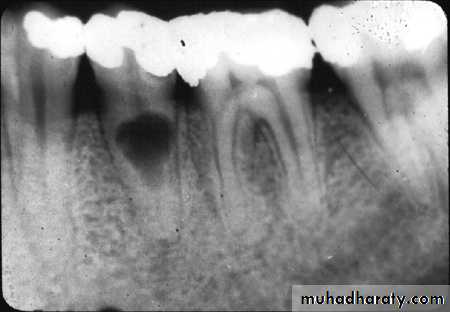

• Radiographic changes show:

– Chronic apical periodontitis in longstanding cases.

– In young patients, low grade longstanding irritation stimulates periapical bone deposition, i.e. condensing osteitis. Radiograph shows areas of dense bone around apices of involved teeth.